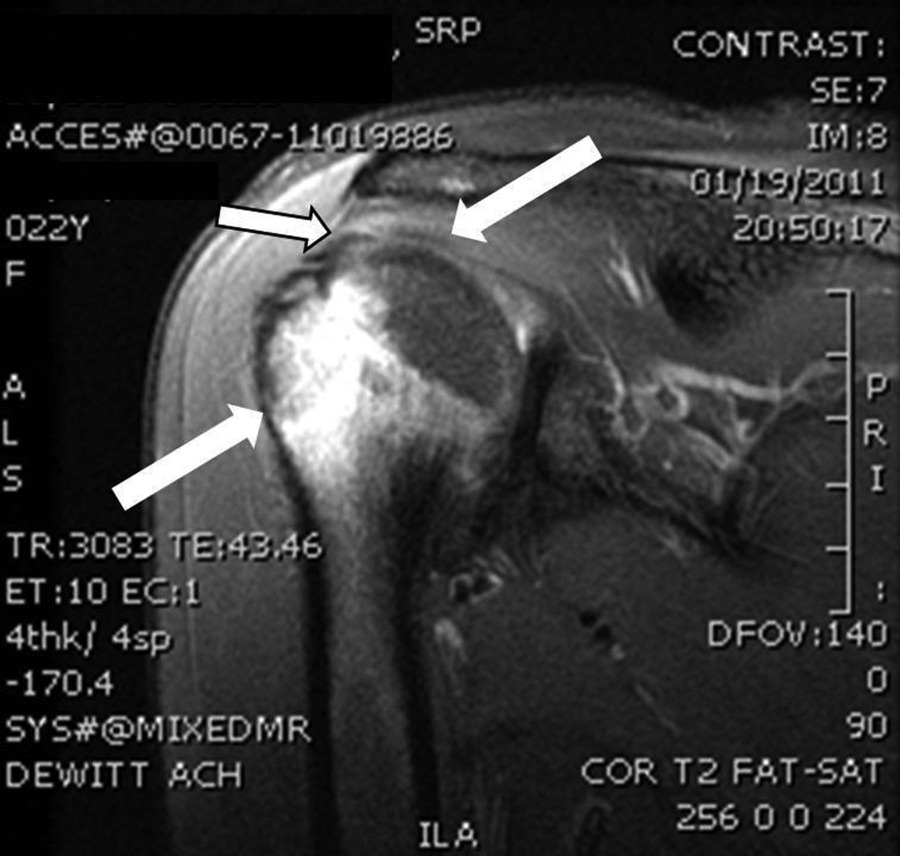

This means that the MRI chances of accurately detecting the possibility of a partial rotator cuff tear are actually there is about 52% Basically the same accuracy odds as a coin Once this 52% is separated into probable and non-probable, then the probable partial rotator cuff tears are confirmed as partial tears with a specificity of2%

Rotator Cuff Tear MRI | New Health Advisor

Figure 1: Rotator Cuff Tear This rotator cuff tear is seen in the The muscle is lit up in bright white and you can see a dark spot indicating the Figure 2: Partial Rupture This is a partial rupture of one of the rotator cuff The red arrow indicates the rupture Figure 3: Complete Rotator Cuff Tear